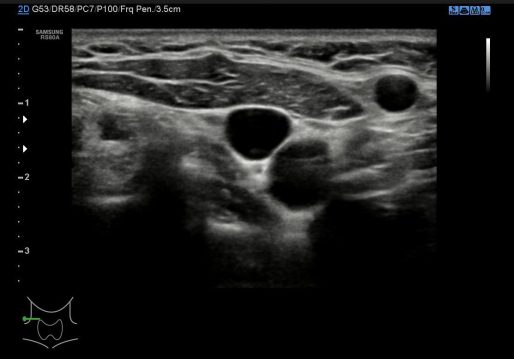

1. Corte axial ambos lóbulos.

En esta imagen 1 buscamos una visualización global de la glándula y nos interesa el aspecto ecográfico de ambos lóbulos.Junto al lóbulo izquierdo observamos la porción visible del esófago.

Colocaremos el doppler color para comprobar vascularización normal de la glándula y sacaremos foto si lo consideramos necesario. (recomendado).

In this image 1 we look for a global visualization of the gland and we are interested in the echographic aspect of both lobes. Next to the left lobe we observe the visible portion of the esophagus. We will place the color Doppler to check normal vascularization of the gland and we will take a photo if we consider it necessary. (recommended).